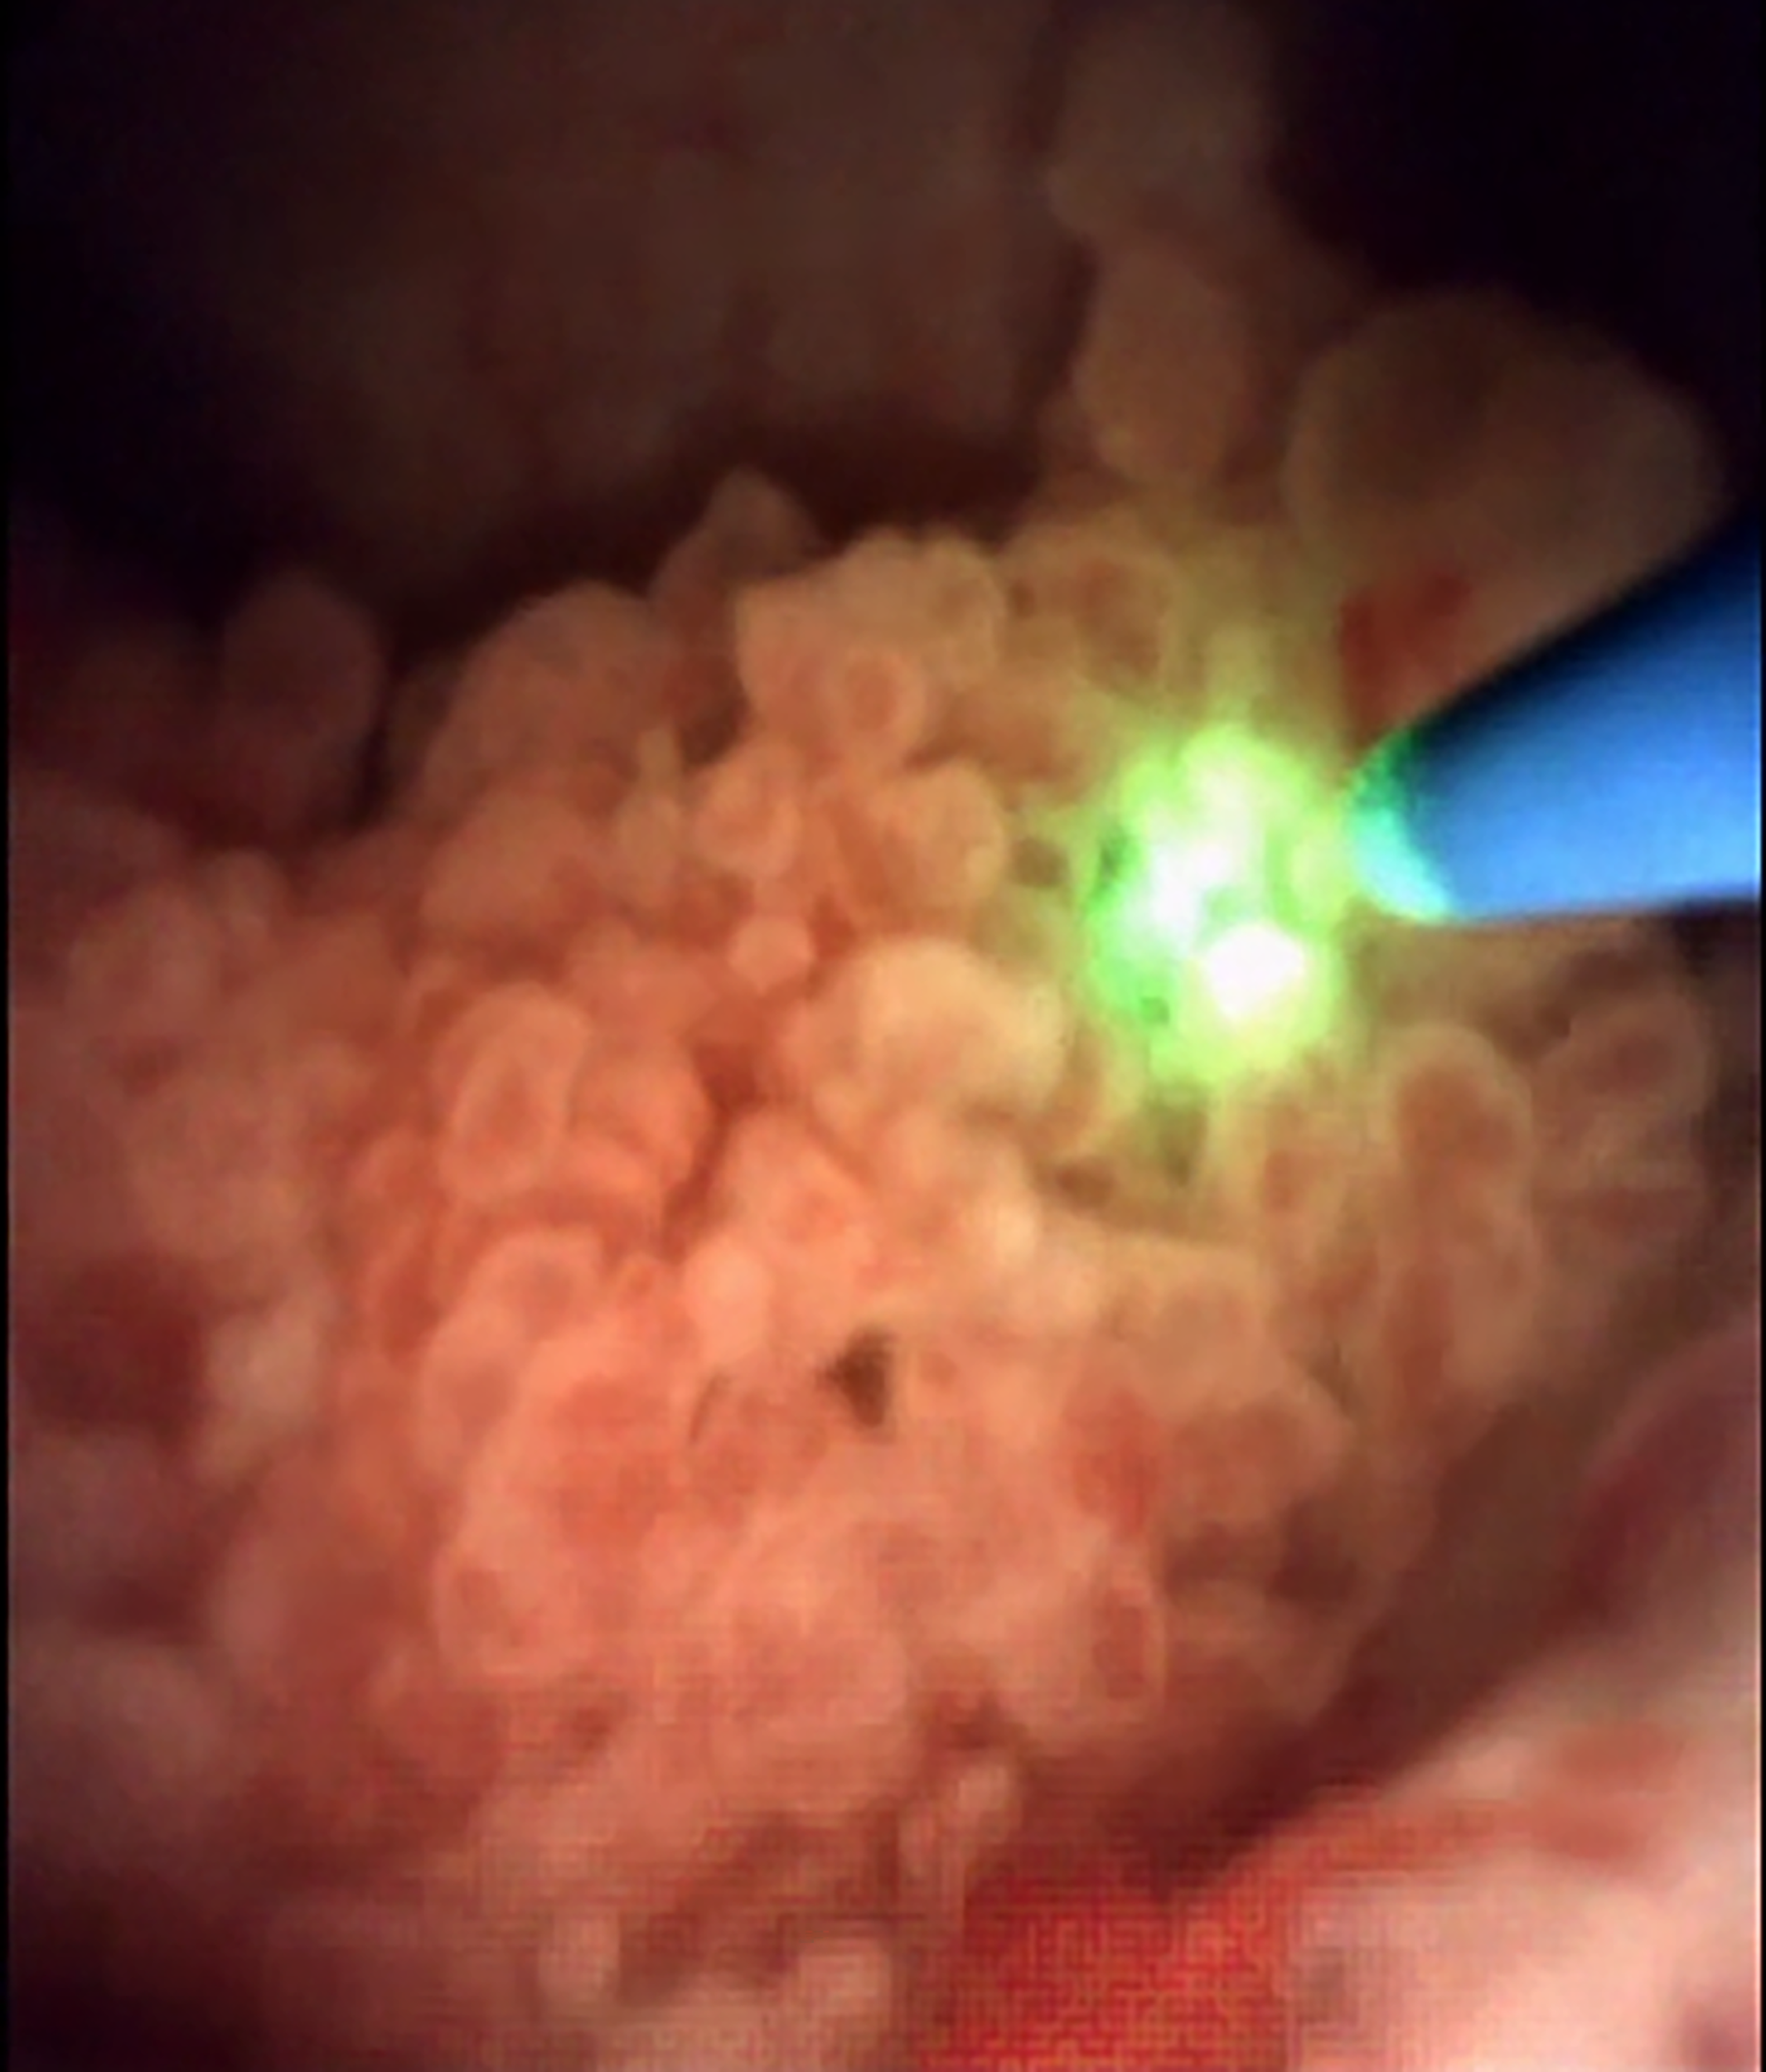

En la actualidad, el principal láser utilizado para esta terapia es el holmio, dada su efectividad y seguridad (profundidad de penetración=0,5mm), aunque también se ha reportado el uso de láser de fibra de tulio (Figura 4). Los parámetros habitualmente utilizados para la ablación mediante láser Ho:YAG son energía de 0,6-1J y frecuencia de 10Hz. Luego de la ablación, rutinariamente se introduce un catéter doble jota, el cual se mantiene por al menos 1 semana50.

Fig. 4. Ablación de CVUA de pelvis renal mediante láser Ho:YAG